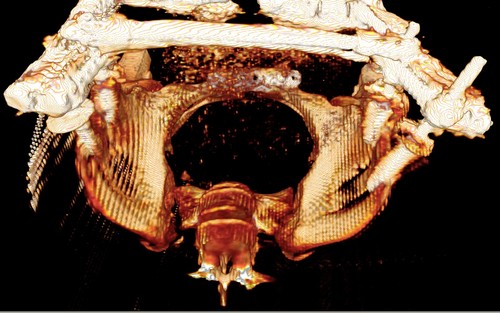

Девочка 14 лет. Кататравма (падение с высоты 4-5 этажа). Вертикально нестабильный перелом таза со смещением, разрывом лонного и левого подвздошно-крестцового сочленения, перелом крестца, открытый перелом костей голени. Ребёнок оперирован на 10-е сутки после травмы - выполнили максимально возможную репозицию на ортопедическом столе, синтез лонного сочленения реконструктивной пластиной (из имеющихся пластин - на 7 дыр - самая длинная, получилось только по 2 шурупа с каждой стороны, поэтому пришлось подстраховаться проволокой), АВФ. Задний комплекс не фиксировали ввиду отсутствия канюлированных (да и неканюлированных)шурупов должной длинны.В настоящий момент перед нами стоит вопросов:1. Обязательно ли фиксировать подвздошно-крестцовое сочленение, либо фиксации АВФ будет достаточно? Аппарат стоит достаточно стабильно, девочка при перемещениях в пределах постельного режима болевых ощущений не испытывает.2. Что делать с отломком крестца, который довольно значительно смещён кпереди? В настоящий момент никаких проблем с дефекацией у больной нет, хотя, глядя на КТ, создаётся впечатление, что отломок прямо-таки лежит на прямой кишке. Репонировать-фиксировать? Просто удалить? Вообще не трогать? Не создаст ли он в дальнейшем проблем во время родов?Хотелось бы знать мнение уважаемых коллег.Заранее спасибо.